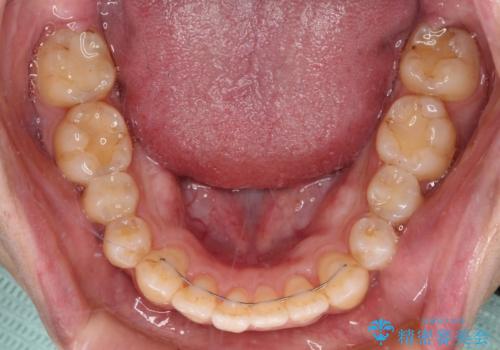

オープンバイトと目立つ銀歯 インビザライン矯正とセラミック修復治療

銀歯については、矯正治療により咬合関係を改善し、矯正治療後半に修復治療を行うこととしました。

修復治療後に細かい部分をインビザラインで再度仕上げるプランとしました。

銀歯のセラミック治療が1番の希望であったため、ここまで歯列がきれいに整うとは思ってなかったようで、大変喜んでいただけました。